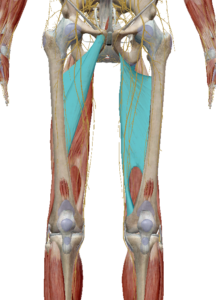

(8) 봉공근

봉공근은 장골의 전상장골극에서 슬관절 내측으로

지나가는 근육입니다.

대퇴골에 직접적인 연결은 없지만 고관절을 지나가기 때문에 고관절 움직임에도 관여하고 제기차기 자세를 만듭니다. (고관절 굴곡, 외전, 외회전)

(9) 대퇴직근

대퇴직근도 장골의 전하장골극에서 시작하여

슬개골을 통해 경골조면에 연결되어 있습니다.

수축 시 고관절 굴곡 또는 골반의 전방경사를 발생합니다.

(10) 치골근

치골근은 이름 처럼 치골에서 대퇴골로 연결된 근육입니다.

수축 시 고관절 굴곡과 내전, 내회전이 발생합니다.

(11) 박근

박근은 치골에서 슬관절 내측으로 연결된 근육입니다.

수축 시 고관절 굴곡과 내전, 내회전이 발생합니다.

(12) 내전근 그룹

내전근 그룹은 왼쪽부터 단내전근, 장내전근, 대내전근으로 이루어집니다.

공통적인 기능으로는 고관절의 내전과 내회전입니다.

대내전근(오른쪽 사진)은 좌골 아래 넓게 연결되어 있기 때문에 슬굴곡근 처럼 고관절 신전의 기능도 합니다.

(13) 슬굴곡근